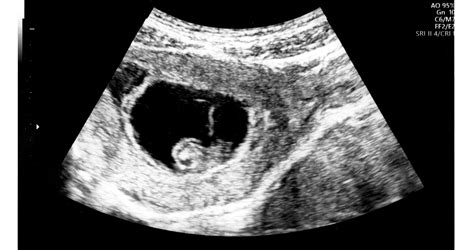

- Ultrahang-vizsgálat: Jellegzetes, "lépesméz-szerű" vagy "hóförgeteg-szerű" képet mutat. Teljes mola esetén magzati szerveket nem látunk.